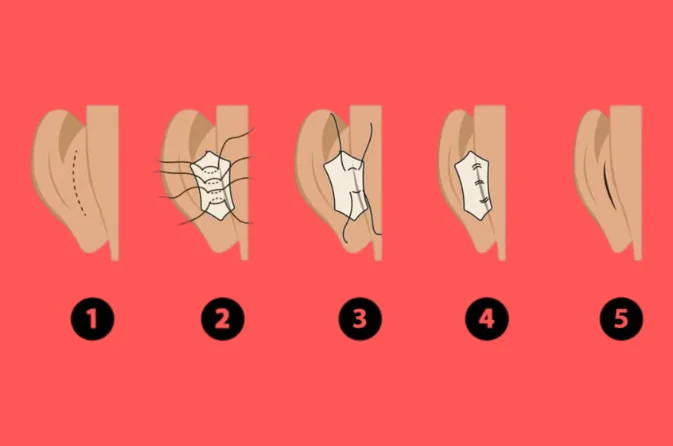

What is Ear Pinning Surgery?

Ear pinning surgery, or otoplasty, is a cosmetic procedure that corrects prominent ears by reshaping and repositioning them closer to the head. It is commonly performed on children and adults who feel self-conscious about their ear shape or size. The surgery is typically done under local or general anesthesia and involves minimal scarring. Recovery is quick, with most patients returning to normal activities within a week. The procedure provides permanent results, offering a more symmetrical and proportionate facial appearance.